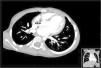

Case 2A 3-year-old asymptomatic boy was referred due to a murmur suggestive of a ventricular septal defect. In the echocardiogram, a turbulent flow was evident in the proximal ascending aorta, as well as in the right ventricular wall. In order to clarify the morphology of this apparent fistulous tract, he underwent a cardiac computerized tomography scan, which confirmed the presence of a fistula between the ascending aorta and the RV (Figure 2).